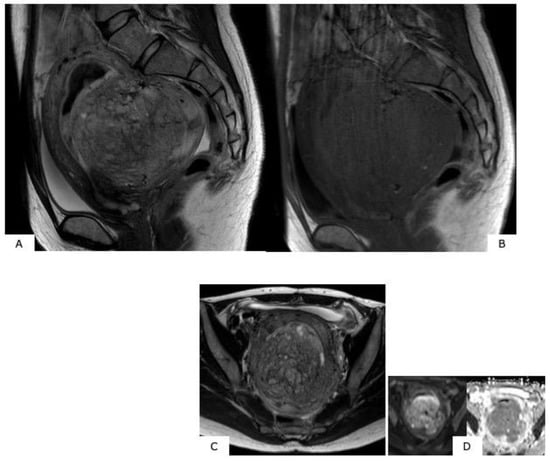

Figure 3.

Magnetic resonance image findings considered to be characteristic of (specific for) uterine sarcoma. (1) High signals in T2-weighted images (T2WI) (case of uterine myoma): Mass in the fundus uteri has extremely high signal intensity (SI). (2) High signals in T1-weighted images (T1WI) (case of uterine sarcoma): There are mottled portions of high SI suggesting hemorrhage within the mass. (3) Ill-defined mass borders (case of uterine sarcoma, T2WI): Mass existing in the myometrium. High signals are presented in T2WI, and at the arrow portions, borders are ill-defined.